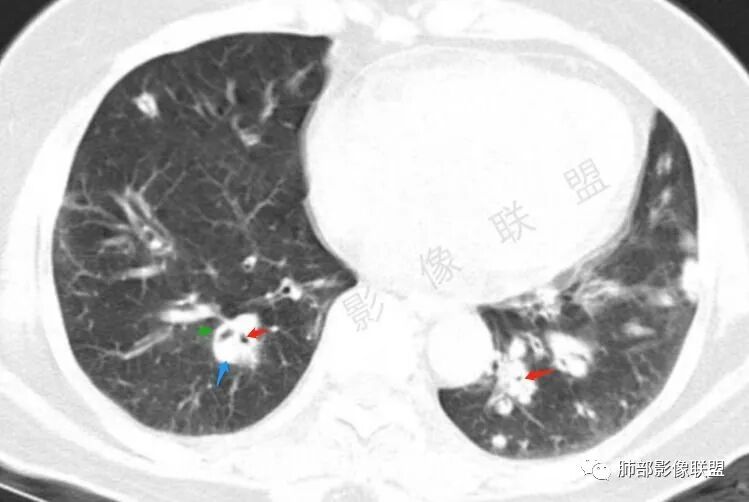

胸CT:双中下肺支气管壁明显增厚,双下肺胸膜下可见实变区。部分病变呈楔形影。

老年女性,咳嗽咳痰低热20天,双肺野散在结节影,随机分布,双肺下叶支气管血管束增粗,支气管管腔狭窄,胸膜下结节斑片影,临床有血尿,痰培养白念阳性,低氧血症。血管炎抗体阴性。从影像看主要侵犯的是血管,血管壁增厚,血管炎抗体阴性不大支持,患者有血尿,考虑膀胱肿瘤引起转移,但是膀胱彩超没发现占位,估计血尿是膀胱炎引起。从影像看考虑侵袭性曲霉菌病?血管炎?实在没有思路。

双肺多发大小不等结节,周围伴有晕征,边界模糊,部分结节内似可见支气管影,双肺血管束明显比支气管增粗,临床有感染症状,考虑GPA,疱疹病毒。

双肺支气管管壁弥漫性增厚,管腔狭窄,下叶为主,伴多发高密度结节影,边缘模糊,双肺支气管血管束明显增粗,临床症状咳嗽低热,有血尿,首先考虑血管炎

影像上:多发结节沿血管分布;双下叶支气管血管束简直增厚,偏血管,支气管通畅

因为支气管壁增厚,远端应该小气道病变,这个不是,反而是血管增粗明显

加上结节的分布,支持血管相关病变

两肺多发结片影,这个病灶很小,但是中间可见支气管影,支气管炎一般不会包在支气管周围,支气管周围间质可能大,包括血管,淋巴等。一般支气管这样穿行的,被包绕的,血管炎,淋巴瘤等这种间质起源比较多见

提示一个支气管周围的间质性病变,并且形成肉芽肿